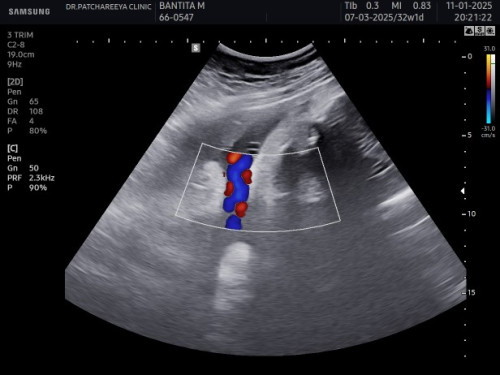

สายสะดือพันคอ1รอบ

ช่วงนี้ รพ.ไม่ซาวด์ให้ดูเลย เป็นห่วงลูกมากค่ะ ในภาพคือไปซาวด์ที่คลินิก แบบเสียตังค์เอง อยากให้ รพ.รัฐ ซาวด์ดูสุขภาพเด็กทุกเดือนบ้างจัง นี่มีแต่ฟังหัวใจรับยากลับบ้าน เอะอะจะให้แต่เราฝากพิเศษอย่างเดียวเลย